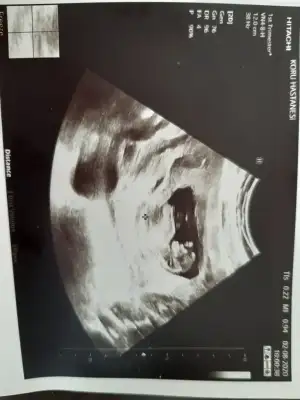

Kızlar ilk kez bugün bebeğimi gördüm ne kadarda büyümüş çok mutlu oldumm :)

Cinsiyet tahmininden anlayan varsa tahminleri alabilirim 🥰